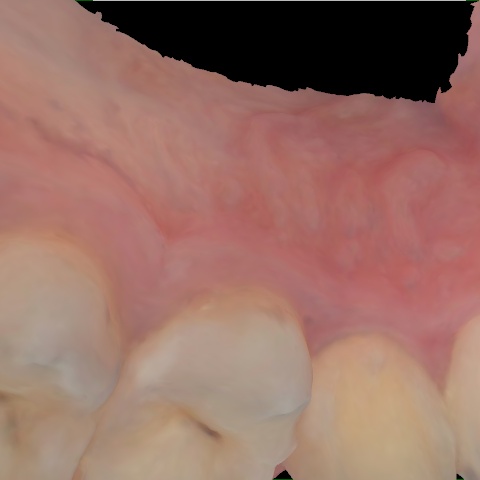

Annotated as "Good"